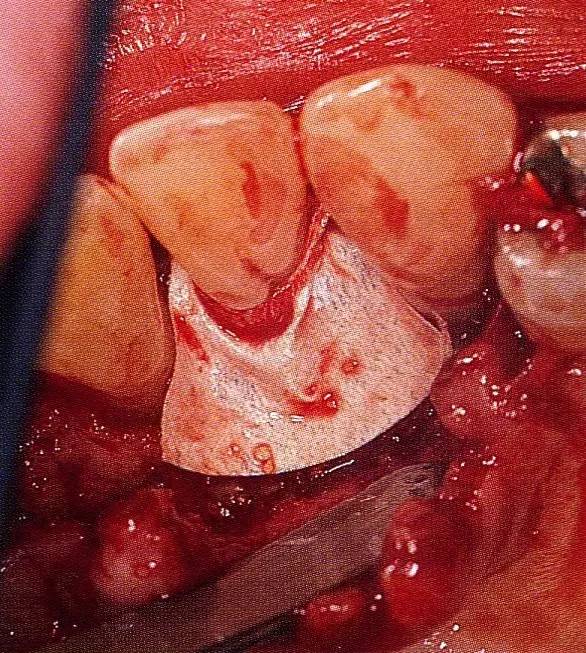

▲圖8-4,5  為了確保足夠空間實(shí)現(xiàn)更好的再生,使用了2張鈦強(qiáng)化型gore-tex膜。

▲圖8-6  通常,會(huì)將覆膜通過縫合線固定在牙齒上,但是,此情況下,使用了鑷子將覆膜進(jìn)一步往根尖側(cè)固定。